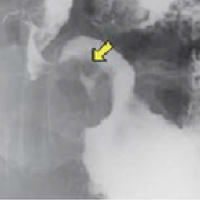

기초검사와 일반검사에서 얻은 자료를 토대로 각종 영상판독 소견을 종합하여 종합검진결과를 완성합니다. 검진결과를 참고하여 필요한 경우에는 개인맞춤 처방을 제공합니다. 또한 내과외래 진료도 진행하여 환자들의 내과진료를 담당합니다. 소화기 내과에서는 위/대장 내시경 검사 및 판독결과 상담을 통해 소화기질환 및 암검진에 대한 상담 및 처방을 진행합니다.